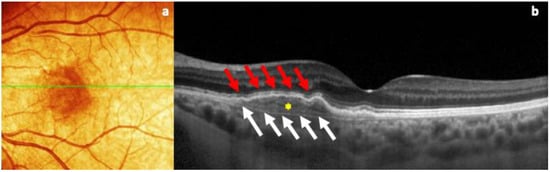

In the fundus examination, the right eye was healthy, with regular tortuosity of the retinal vessels, a trophic macula, and a normal optic disc, in the absence of retinal lesions. On the other hand, the left eye showed an RPE alteration with a slight yellowish retinal elevation in the interpapillo-macular region. For this reason, an OCT evaluation (Spectralis; Heidelberg Engineering; Heidelberg, Germany, version 6.0) was performed to better determine this retinal finding, which revealed an irregularly slightly elevated RPE, characterized by collections of moderately reflective material in the sub-RPE area and strong visualization of the Bruch hyperreflective membrane with a large axis in the horizontal plane, with no signs of exudation (Figure 1).

Figure 1. (a) OCT color fundus image of the quiescent MNV, showing the presence of slightly hyperpigmented flat lesion, with indefinite edges, in the macular region. (b) B-scan OCT image of the same retinal lesion, characterized by the visualization of two hyperreflective layers (double-layer sign): retinal pigment epithelium (red arrows) and the Bruch membrane (white arrows) with a major axis on the horizontal plane, with the presence of reflective material inside (yellow asterisk), in the absence of subretinal fluid.